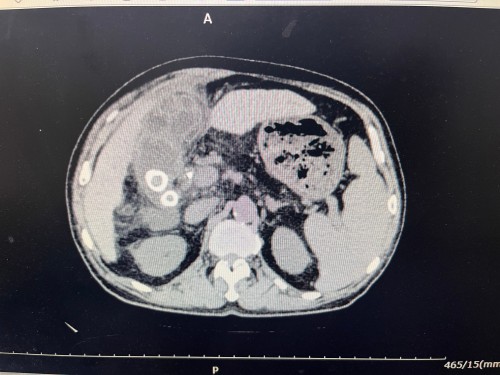

入院时,患者感染指标显著升高,腹部体征明显。CT提示,胆囊壁增厚,其内可见环状高密度影,肝内外胆管积气,胆囊区域炎症包裹严重,局部结构因前期介入操作及引流管而变得更为复杂、紊乱。腹腔内尤其是右上腹区域已形成广泛、致密的纤维黏连,解剖间隙几近消失。这种情况若行传统开腹手术,创伤大、恢复慢;若行常规腹腔镜手术,则极易因黏连严重、视野不清而导致副损伤,手术难度呈几何级数增加。